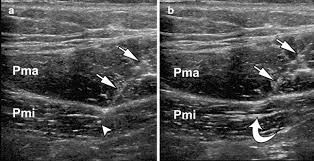

We studied the effect of botulinum toxin type A BTX-A injections to the scalene muscles on pain in subjects with thoracic outlet syndrome TOS in this double-blind randomized parallel group trial with follow-up at 6 weeks 3 months and 6 months. Botulinum toxin injection under ultrasound guidance is a safe and well-tolerated procedure with a. Results and experience using a ultrasound-guided approach.

Botulinum toxin injection under ultrasound guidance is a safe and well-tolerated procedure with a satisfactory rate of temporary symptom relief in subjects with suspected NTOS. Johns Hopkins researchers have found that patients with a painful and debilitating nerve compression disorder called thoracic outlet syndrome TOS which studies suggest may occur in up to 8 percent of the population reported a significant reduction in short-term pain after receiving a single low-dose injection of Botox in a muscle located in the neck. Scalene muscle injections are used to confirm the diagnosis of neurogenic thoracic outlet syndrome and predict the response of patients to surgery.